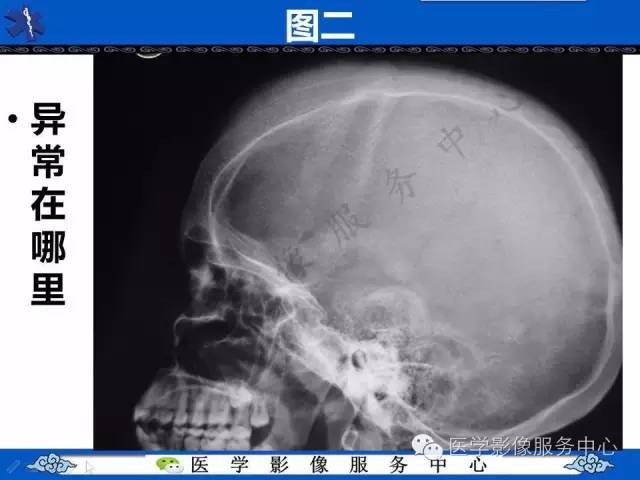

【影像征象】竖毛征——重度贫血